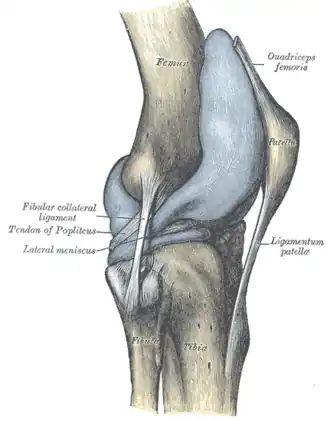

Capsule of right knee-joint (distended). Lateral aspect. | |

The superior tibiofibular articulation (also called proximal tibiofibular joint) is an arthrodial joint between the lateral condyle of tibia and the head of the fibula.

The contiguous surfaces of the bones present flat, oval facets covered with cartilage and connected together by an articular capsule and by anterior and posterior cruciate ligaments.